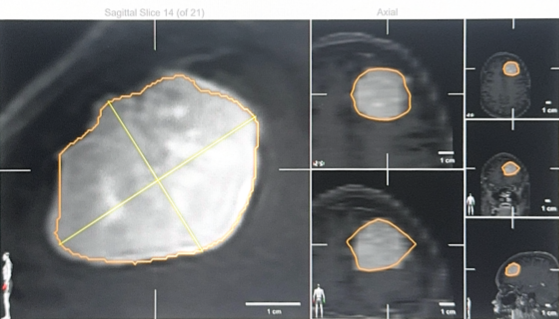

他介绍道,新技术能大大提升手术的精准度和安全性。比如,多模态神经影像导航系统就像车载GPS,能实时显示探头与肿瘤边界的位置,误差不足一毫米,避免“误伤”;数字荧光显微镜能让肿瘤与正常脑膜像“亮灯”一样区分开来;遇到坚硬或血供丰富的肿瘤时,超声吸引系统会把肿瘤组织“化开”并同时吸出,缩短手术时间;而神经内镜则能看清显微镜难以触及的角落,帮助医生把病灶切得更干净。

多模态神经影像导航系统让手术切口更小,操作更精准,病人恢复也更快

“用大白话讲就是——有了这些技术,手术切口更小,操作更精准,病人恢复也更快。”叶晶亮的解释,让冯女士心里的石头终于落了地,她坚定了在克拉玛依接受手术的信心。